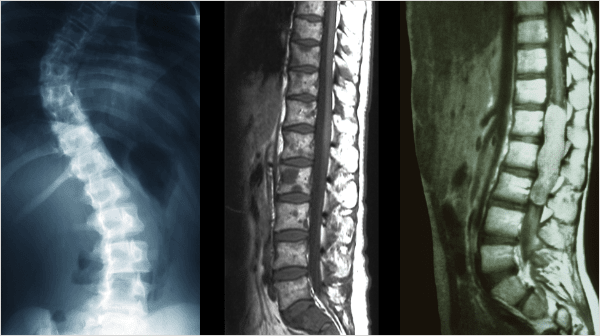

척추측만증,후만증,전만증

추의 만곡이 소실되어 척추가 왼쪽 혹은 오른쪽으로 휘어지는 증상을 척추측만증,

허리뼈가 아무런 굴곡없이 일자로 꼿꼿한 허리를 후만증, 앞쪽으로 휘어지는 증상을 전만증 이라고 합니다.

정상

비정상